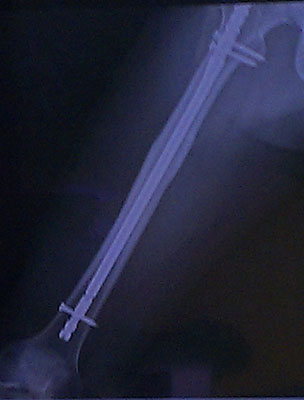

Thigh Fracture

A 18-year old male student happened a tight fracture on a traffic accident. He and his family didn・t know the MDD at the time. After spending 1 year of convalescing, he bravely requested a surgical operation to remove the titanium stand. In order to ease pain, prevent cold leg, release uncomfortable and enhance microcirculation, he used the MDD for 2 weeks over the lower leg while sleeping and resting. He found that it is less pain, less uncomfortable, and faster recovery on muscular and nervous tissues compares to the first surgical operation.

Precaution: The MDD offers vascular dilation and constriction thus enhancing better metabolism and providing faster blood flow. If it uses on bleeding wound (no mater external or internal bleeding wound), it will cause more bleeding, and therefore it can・t be used on bleeding wound. In this case, the wounded part is in the upper leg, at the end of limb (lower leg) also felt cold and uncomfortable due to poor blood circulation. These are the reasons the MDD is used over lower leg instead of upper leg.